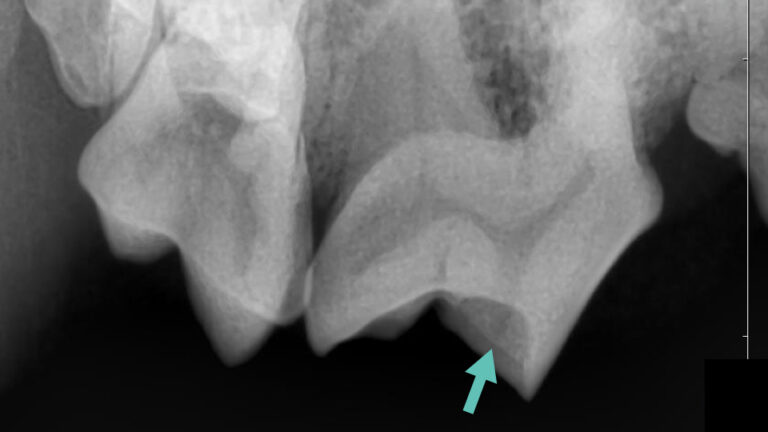

下の写真を見てみましょう。

これはプロービングと言って歯周ポケットの深さを測る検査です。

歯肉はそこまで後退していないのに対して、写真2枚目の犬歯裏側の歯周ポケットは非常に深く、

歯科レントゲンでも歯槽骨の融解を認めました。